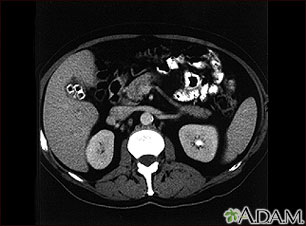

Tests that reveal gallstones or inflammation in the gallbladder include:

- Abdominal ultrasound

- Abdominal CT scan

- Gallbladder scan (HIDA scan)

- Oral cholecystogram (rarely done)